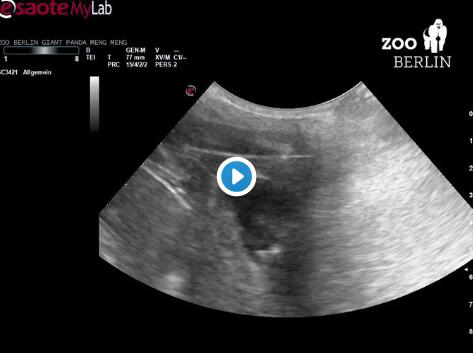

图为梦梦的超声波图像。(图片截取自柏林动物园推特)

园方在社交平台推特上公布了梦梦的超声波图像,配文称图中显示出一只“心脏快速跳动的小熊猫”。据园方介绍,梦梦至少怀有一只幼崽,并且可能会在未来一两周之内生产。